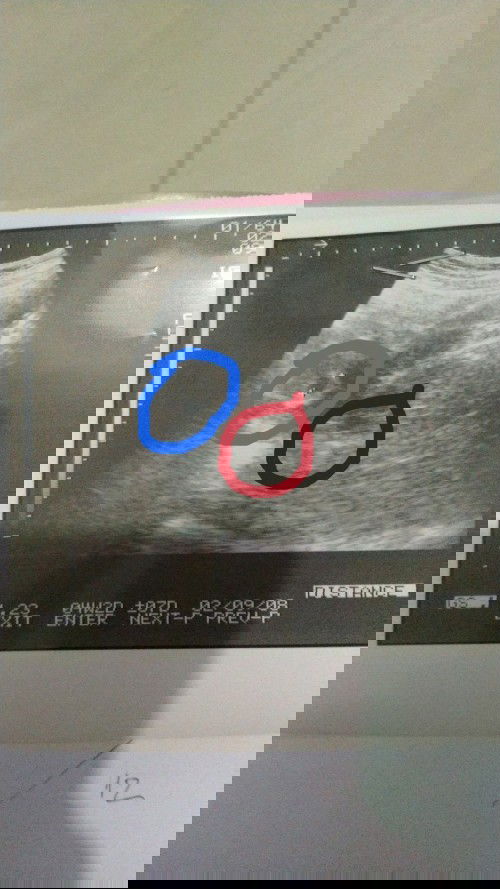

Bunda sedikit bertanya, semalam saya USG kehamilan, terbaca usianya 4 minggu. Di jelaskan oleh dokter adalah yang saya lingkari biru (kantong nya sudah keliatan menebal). setelah saya sampai rumah saya amati lagi ternyata ada 2 kantong. Yang saya tanyakan adalah lingkar merah ini kira² bentuk 2 kantong atau lingkaran apa ya bunda, atau memang bentuk USG 4minggu memang seperti itu? #seriusnanya #bantusharing #ingintahu #pleasehelp #firstbaby #firstmom